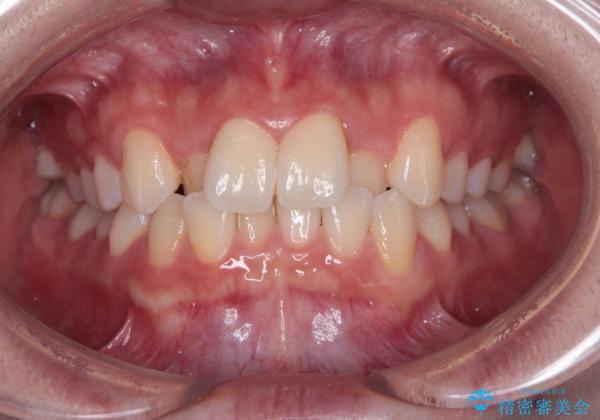

前歯のクロスバイト 裏側に隠れた歯をワイヤー装置で短期間治療

想定通り、1年強で綺麗に仕上げることができました。